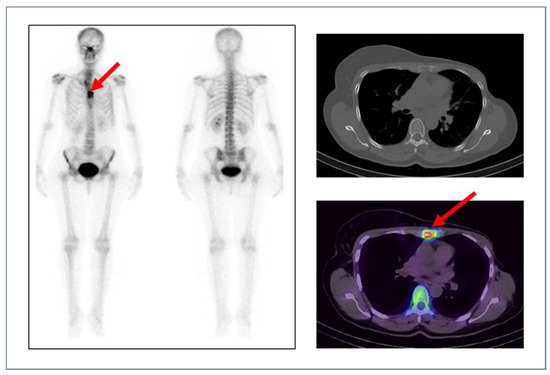

Figure 6 presents the case of a 41-year-old female at a follow-up for left breast cancer. The scan was performed post-left modified radical mastectomy (MRM) and post-chemotherapy with tamoxifen. The patient presented with anterior chest pain; a bone scan was performed for the evaluation of chest pain. The bone scan shows abnormal osteoblastic activity in the sternum (on whole-body planar images) which localises to an osteolytic lesion seen on SPECT/CT fused images, suggesting the diagnosis of bone metastasis.

Figure 6.

Anterior and posterior whole-body bone images show abnormal radiotracer uptake in the sternum as pointed out by the arrow (left). CT and fused SPECT/CT (right top) and (right bottom) images of the chest show abnormal tracer uptake (seen as a hot spot on the image) in the sternum at the site of the osteolytic lesion as indicated by the arrow.